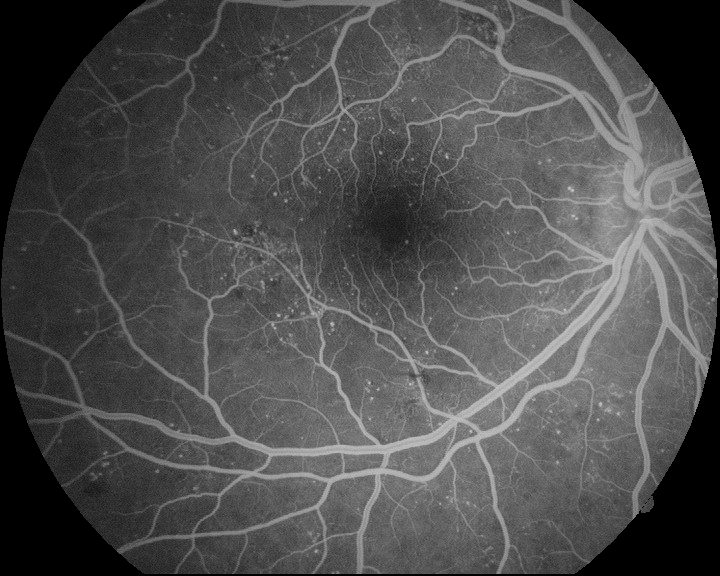

Several experiments are conducted to evaluate the hybrid methodology as well as the performance of the FBR and IBR methods. Regarding the IBR method, both the affine transformation (IBR-AT) and the free form deformation (IBR-FFD) variations are applied. We propose the hybrid method formed by the sequential application of FBR, IBR-AT and IBR-FFD, and alternative variations over this by removing one or two steps at a time. This results in 7 different configurations of methods, as reported in Table 1. The table shows the average and standard deviation VE-NCC for each method in healthy and pathological cases. Figure 3 depicts the cumulative distribution of the VE-NCC values. The best results are achieved by the proposed hybrid method. There is a large difference between the experiments that perform the initial FBR and the ones that directly apply IBR. For the latter experiments the registration failed in most of the cases. Most of the image pairs do not significantly change their VE-NCC values by applying IBR alone, and only a few of them obtained values over the minimum that was achieved by the initial FBR. These results indicate that, with the use of IBR and high order transformations, more accurate registrations can be achieved. However, they also evidence the importance of a proper initialization for the convergence of the optimization algorithm, which is provided by the initial FBR. Moreover, the IBR-FFD also benefits from the previous IBF-AT, as the order of the applied transformation directly fixes the search space dimensionality, increasing the complexity of the optimization. Figure 4 exposes some representative examples of the images registered with the proposed hybrid method. Both the raw images and the vessel enhanced images provide qualitative evidence of a satisfactory multimodal registration with the hybrid approach in healthy and pathological scenarios.

Refer to caption

Figure 4: Examples of the multimodal registration with the hybrid method: (a)(c)(i) retinographies; (b)(f)(j) angiographies; (c)(g)(k) registered image pairs; (d)(h)(l) results of the vessel enhancement operation applied to the registered image pairs.